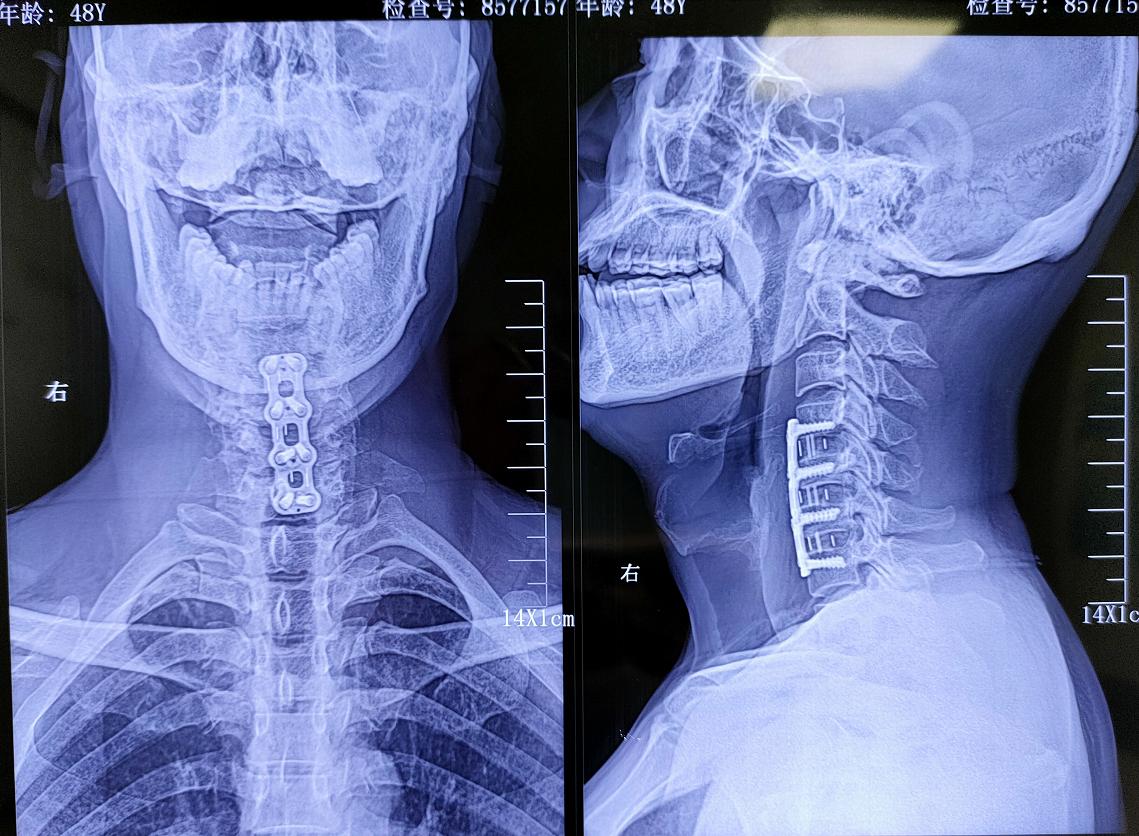

经过廖博主任的劝说,再加上妻子的支持,最终王先生改变了主意,同意尽快进行手术治疗。廖博主任尽快为他安排了手术,并亲自操刀,精细操作下成功完成了“颈椎前路融合内固定术”。手术完美解除了脊髓受压情况,并有效限制了颈椎异常屈曲、扩大硬膜囊容积,有效阻止了病情进展。

术后影像学资料:

“手术完了当天醒过来,我感觉全身都轻松了,原来疼的地方全部不疼了,这种久违的感觉真舒服……”手术后,王先生的症状消失,情况一天比一天好,这也让他天天都乐呵呵的。